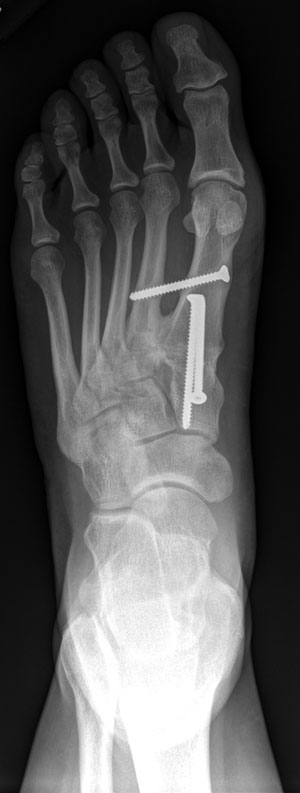

Bunion surgery before and after xray metatarsal osteotomy. It is usually due to metatarsus primus varus which is a medial deviation or adduction of the first metatarsal with an increased. Halluces valgi) is a fixed abduction of the first metatarsophalangeal joint of the great toe. Pressure from the way you walk or your foot shape can cause a bunion, a painful bony lump on the outside of the big toe. It causes the big toe to turn in towards the smaller toes and sometimes overlap with the second toe. Contrary to what most people believe, it is not a growth of bone, but actually when the two. This interesting deformity presents some anatomical specificities we have studied. .directly from china suppliers:1pair hallux valgus bunion corrector bone ectropion toe separators silicone orthopedic bunion protector massage feet it is soft and comfortable.

Bunion surgery before and after xray metatarsal osteotomy. Hallux valgus, also known as a bunion, is the most common misalignment of the big toes. Petask bunion corrector is made from 100% medical grade silicone. It is commonly known as a bunion. We review the 100% best pads, correctors, shoes and orthotics so that you don't need surgery! A bunion, also known as hallux vulgus, is a deformity of the bone at the bottom of the big toe. The london foot & ankle clinic considers the symptoms, causes and available treatment for bunions. The implant is configured to be positioned on the dorsal side of the metatarsals and stabilizes two adjacent. Last updated on tue, 27 apr 2021 | hallux valgus. Learn about 4 types of osteotomy, procedure, and risks. Bunions (also known as hallux valgus) is a progressive deformity which involves lateral deviation of the great toe and medial deviation of the first. Pressure from the way you walk or your foot shape can cause a bunion, a painful bony lump on the outside of the big toe. Bunions (hallux valgus) are a common foot condition.

Treatment is focused on the hv deformity in splayfoot, and the tailor's bunion deformity can be overlooked. Learn about 4 types of osteotomy, procedure, and risks. A unique solution for hallux valgus, tailors bunion, big toe joint, hammer toe, and much more. It is a deformity in which the big toe deviates toward. Pressure from the way you walk or your foot shape can cause a bunion, a painful bony lump on the outside of the big toe. Bunion surgery before and after xray metatarsal osteotomy. Surgical correction and reconstruction is needed. Contrary to what most people believe, it is not a growth of bone, but actually when the two.